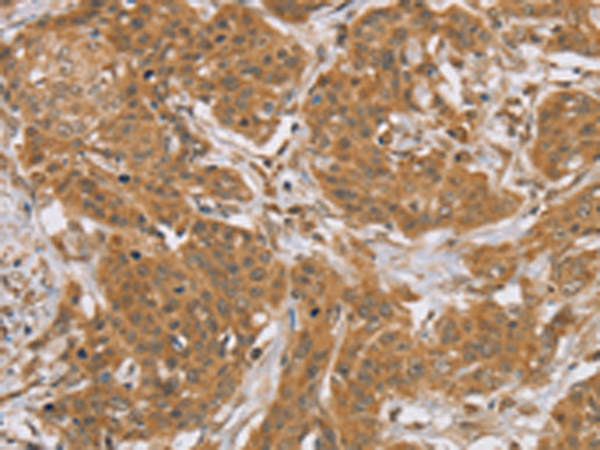

分类: 科研抗体货号: P05179别名: OLD35; DFNB70; PNPASE; old-35; COXPD13应用: WB,IHC反应种属: Human, Mouse